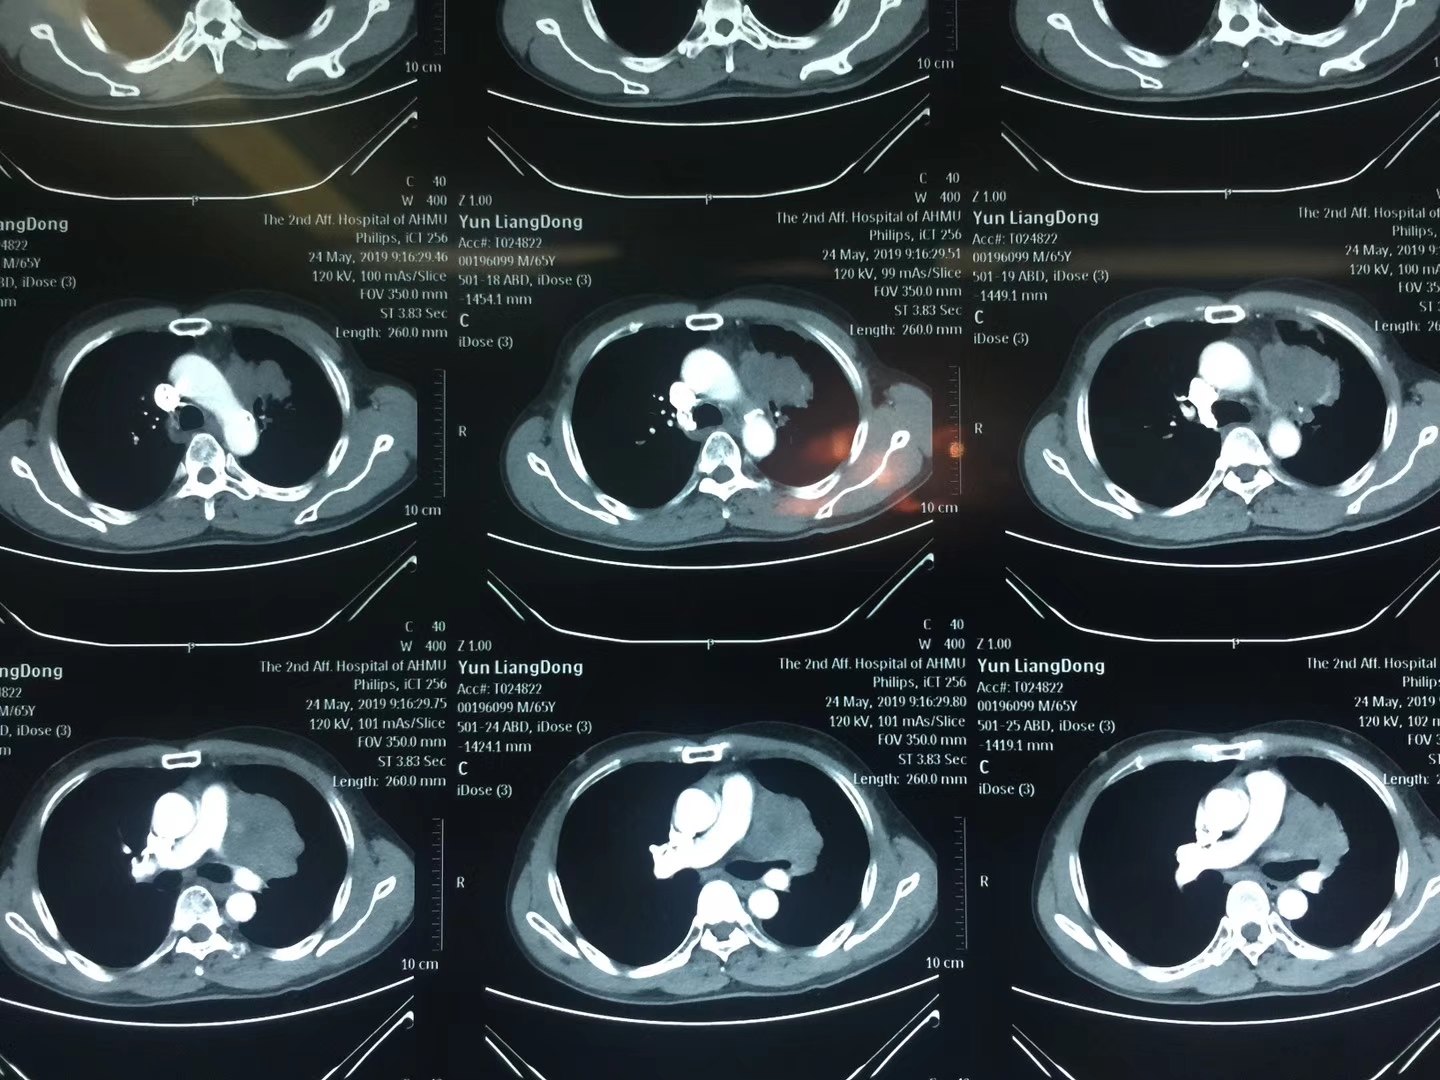

mmexport1579392826720.jpg

结论: 从以上肺癌的发生、发展过程,我们可以看到,“越小的肺结节是良性的可能性越大,不用管它”的观点是不对的!我们应该意识到:再小的肺结节也有可能癌变。